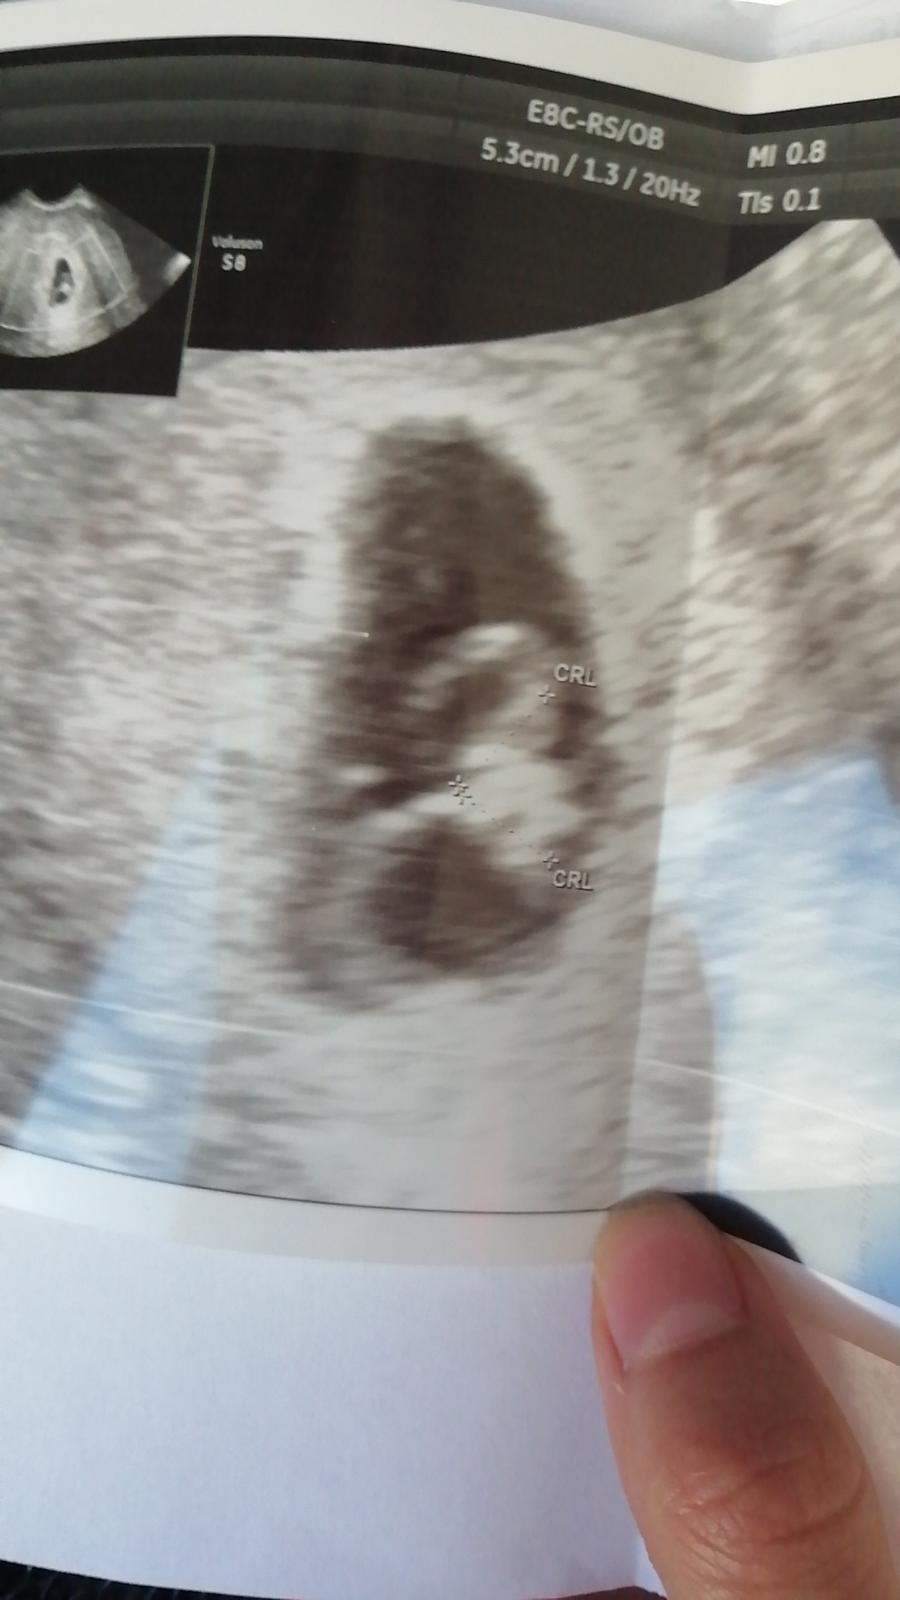

Nemáte náhodou niekto skúsenosť? Dnes som bola prvý krát na Sone podľa ms som 8+4 ovulka mi vychádzala týždeň po MS aj testy mi začali duchov at na 9den po ovulke. Dnes mi doktor oznámil ze sú dne. Jedno ma 0.34cm a druhe 0,37cm väčšiemu srdiečko bije druhému nie a druha vec zodpovedajú 6+0. Povedal ze to menšie pravdepodobne už neprežije. Mates tým niekto skúsenosť? Teraz čakať znova týždeň je pre mňa vecnost☹️